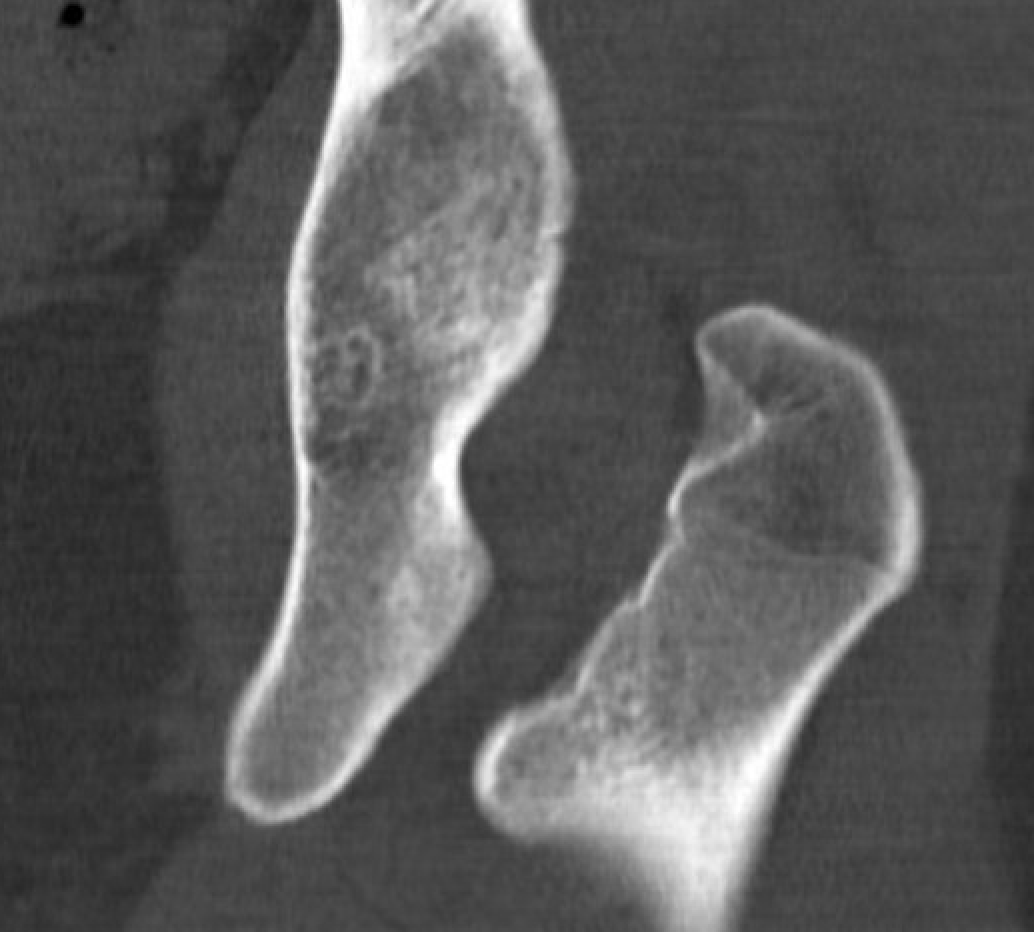

CT

IFI

IFIIFIIFI